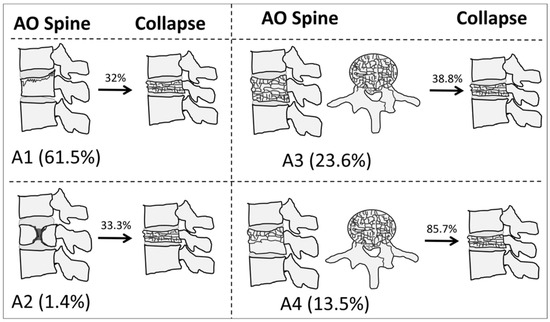

Bivariate analyses showed significant associations between all classification systems, except Genant et al.’s quantitative, and vertebral collapse. The highest rate of collapse among all classifications was observed in the A4 category of the AO Spine, with 24 out of 28 (85.7%) OVFs developing vertebral collapse on follow-up. Figure 1 shows illustrative examples of A1-A4 AO Spine classification fractures, and Figure 2 summarizes the incidence of collapse in these fractures. Table 1 shows the incidence of the different types of OVFs and the results of bivariate analyses.

Figure 2.

The incidence and rate of collapse of osteoporotic vertebral fractures, according to the AO Spine classification system in our sample.

Third, we found that, among the different classification systems explored, only the one proposed by the AO Spine was associated with vertebral collapse. In particular, approximately two thirds of A1 fractures did not collapse. Conversely, 24 out of 28 A4 fractures collapsed in our series, while A3 fractures were very similar in both groups (collapse, 30.8%; non-collapse, 32.4%). The odds ratio for vertebral collapse in A4 vertebral fractures (using A1 as the reference standard) was 15.4, although the confidence interval was ample due to the relatively limited data available for multinomial variables in our sample. The AUC of the model for AO Spine fractures was moderate (0.646) and particularly influenced by the A4 category, with poor sensitivity (28.2%) and high specificity (96.7%), indicating that the model helps predict those fractures which will not collapse. Notably, this model only takes into account the predictive power of the AO Spine classification, which could be significantly increased with multivariate models that should be explored in future studies [3].